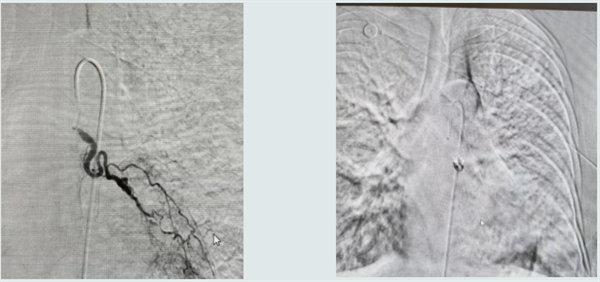

在介入手術室,介入科團隊憑借精湛的技術,快速完成造影檢查,精準鎖定患者左下肺支氣管動脈急性破裂大出血的病灶。隨后,他們熟練地實施介入栓塞術,成功堵住破裂血管,為患者解除了致命威脅。術后,患者生命體征逐漸平穩,安全返回病房,后續接受輸血補液等鞏固治療。